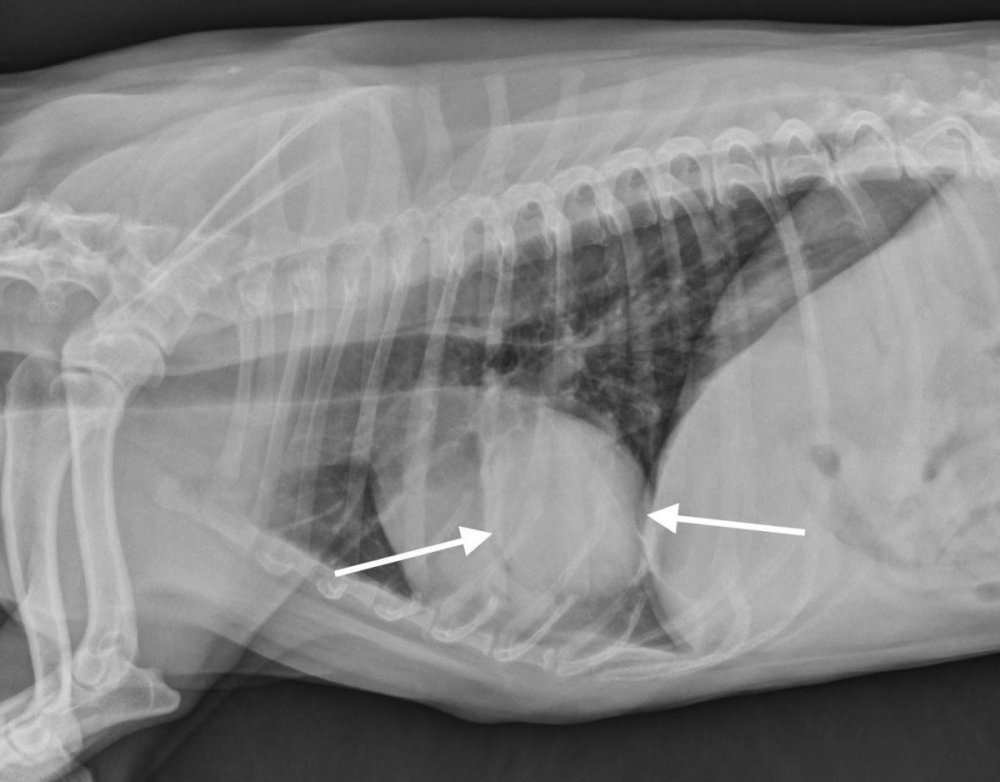

Diagnosis usually happens in layers. A vet will start with a physical exam and history, then move to imaging. Chest X-rays are often the first step, and they can show lung masses, changes in lung pattern, and sometimes enlarged lymph nodes.1, 7

A CT scan can provide a much clearer map of what is happening in the chest, including the size and location of a mass, whether lymph nodes look involved, and whether there are multiple lesions that might suggest spread.1, 7